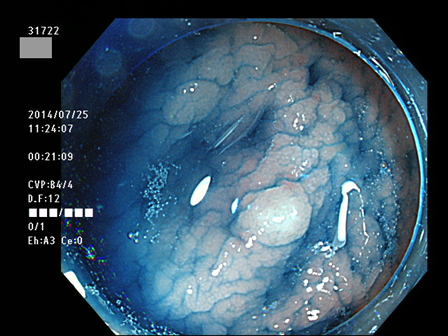

上記100名より抽出した平坦・陥凹型腺腫(=癌化の危険が高いが見落としやすい病変)の内視鏡写真

31764 31765 31766 31767 31768 31769 31771 31774 31776 31777 31778 31779